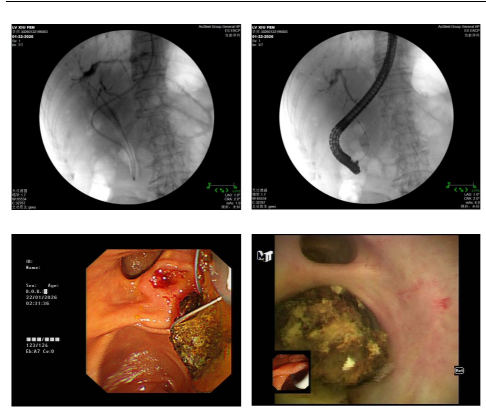

接诊后,消化内科团队对患者病情进行全面评估。影像学检查提示:肝门区及肝内胆管可见多发结石,肝内胆管积气,胆总管扩张,其下段存在高密度影。更为棘手的是,患者因既往多次手术,腹腔粘连严重,若行传统开腹手术,不仅需分离广泛粘连组织,还需再次切开胆总管取石,手术创伤大、并发症风险高,对高龄患者身体负担极大。

面对如此复杂情况,消化内科团队经过深入讨论与综合研判,最终决定为患者实施经口胆道镜取肝内胆管结石术。该技术属于微创治疗,无需开腹,通过口腔将胆道镜送至胆管内,在直视下精准取石,具有创伤小、恢复快、感染风险低等显著优势,能有效规避腹腔粘连区域,极大降低手术风险。

在消化内科乔强主任的指导下,团队凭借娴熟的微创操作技术,顺利将胆道镜置入患者二级肝内胆管,清晰显露出肝内胆管结石,并将结石完整取出。手术过程顺利,术中无出血。术后患者安返病房。